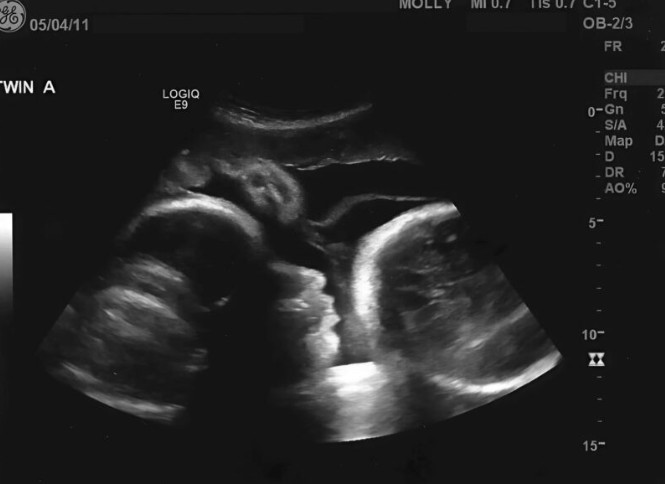

Tek kada su bolovi postali nepodnošljivi, Larisa je odlučila da potraži pomoć. Posetila je ginekologa s uverenjem da će uskoro doživeti porod. Ovaj korak je bio teško doneti, jer je Larisa bila duboko uverena da su njeni simptomi samo prolazna stvar. Kada je lekar izvršio pregled, njegovo lice postalo je bledo, a Larisa je bila šokirana onim što je čula. Umesto radosne vesti o trudnoći, lekar joj je saopštio da njeni simptomi zapravo ukazuju na ozbiljno zdravstveno stanje. Na ekranu su se prikazivali znakovi koji su ukazivali na cistu koja je rasla u njenom stomaku. Ovaj trenutak bio je ključan u njenom životu, jer je suočila sa stvarnošću koju je tako dugo izbegavala. Larisina priča nas podseća na važnost prepoznavanja simptoma i reakcije na njih. Mnogi ljudi, poput nje, često zanemaruju signale svog tela u nadi da će se stvari same od sebe rešiti. U trenutku kada je čula dijagnozu, Larisa je shvatila da su svi njeni simptomi bili rezultat nečega što je zahtevalo hitnu medicinsku intervenciju. Lekari su joj objasnili da je stanje ozbiljno i da se mora odmah lečiti. Ovaj težak trenutak postao je prekretnica u njenom razmišljanju – shvatila je da se ne može oslanjati samo na verovanja i nade, već da je neophodno potražiti stručnu pomoć koja će joj omogućiti da se suoči sa stvarnošću.